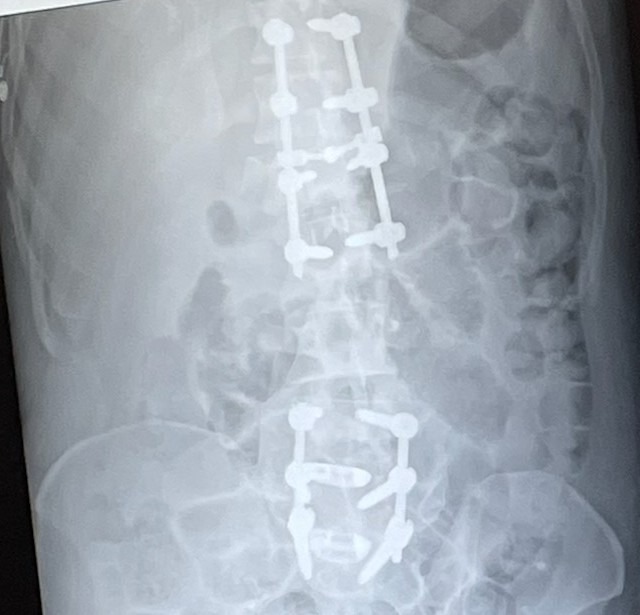

On August 18th, 2023, I had gone to town for a part to complete a small wood project, and as I was going through the green light, a 17-year-old turned into and over my motorcycle. I was airlifted with a broken back, paralyzed, and missing my left leg after amputation, five broken ribs, a plate on my broken collarbone, and road rash. I've had five surgeries just within weeks of the accident. The teenager driving had been on the phone during the accident and afterward didn't even call 911. Later, we found out that she had been driving as a restricted driver under their insurance policy, so no insurance, and I only had liability.